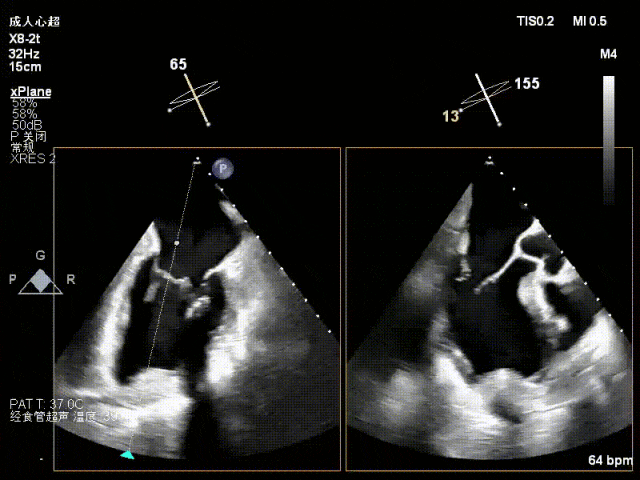

术中超声(关键步骤)

混合性MR,P2脱垂连枷(脱垂范围15mm,连枷间距4mm),腱索断裂

新分型:ACA型,反流2区及两侧,MR 4+,VC:3×14mm

A2:24mm,P2:17mm,AP:38mm,MVA约5.7cm²